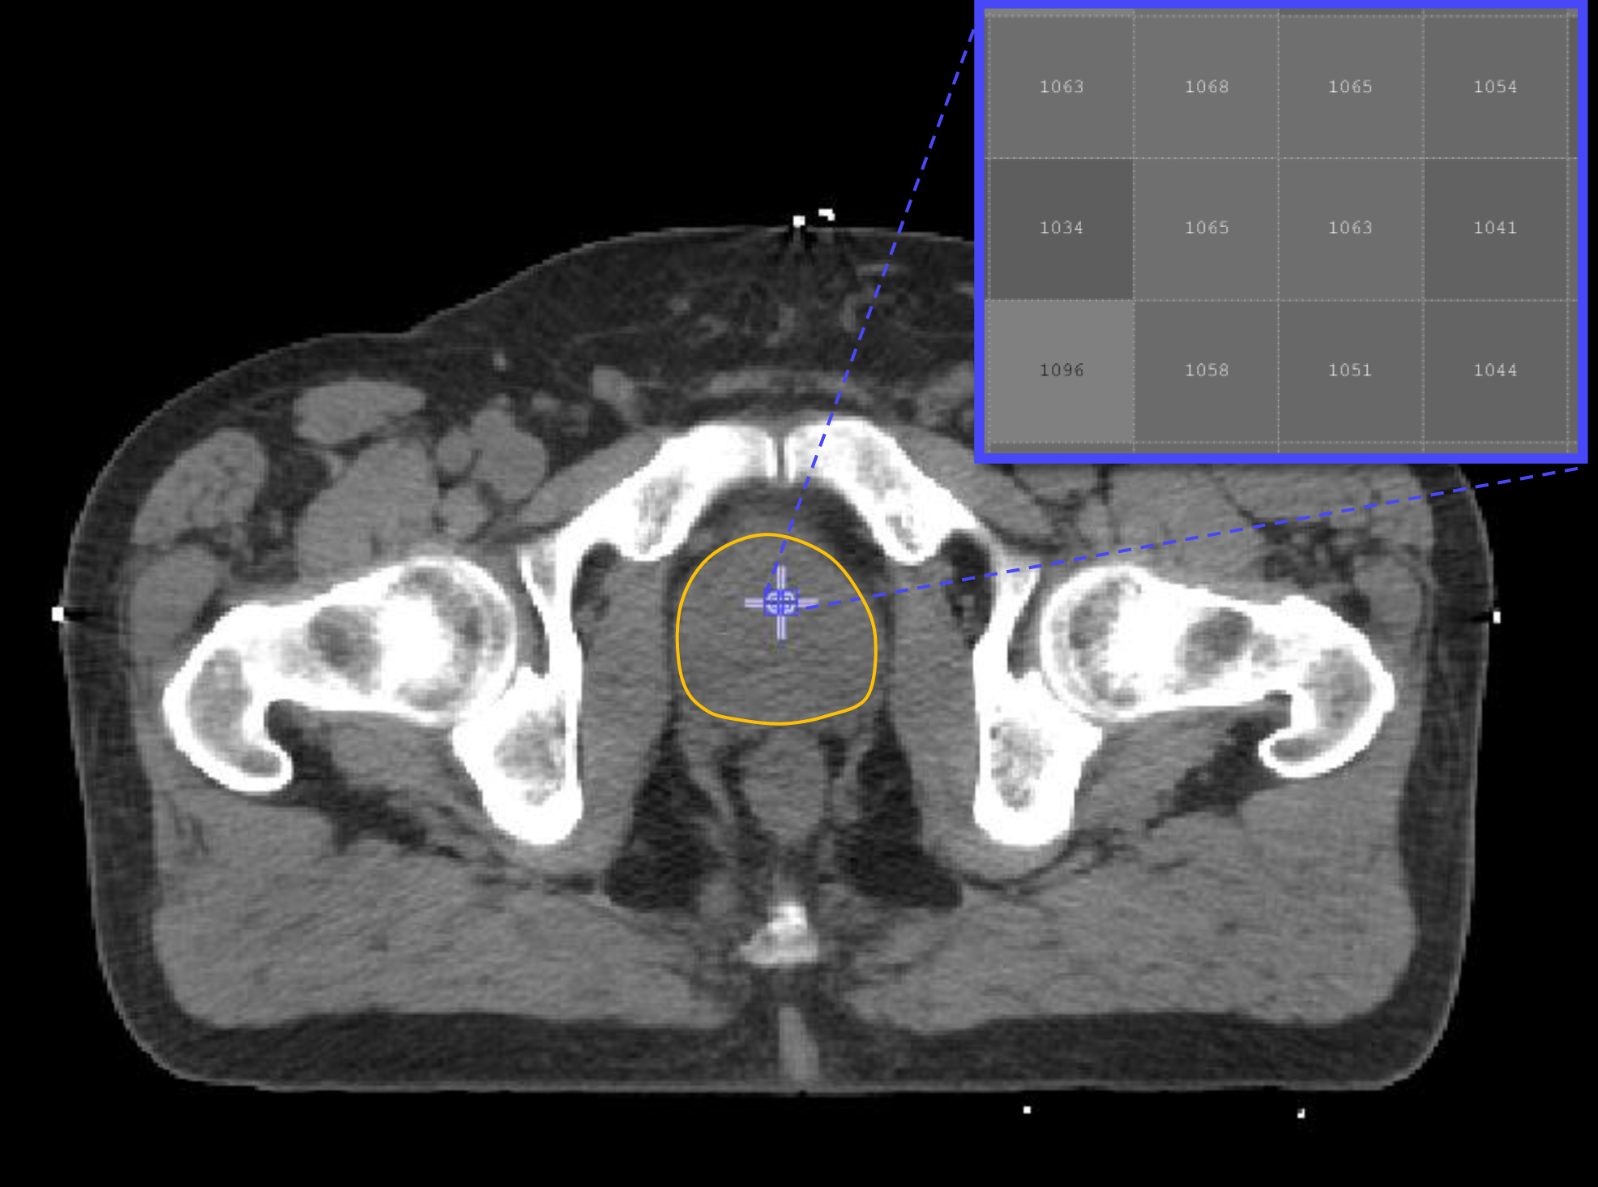

The new method uses images from computed tomography (CT) scans that are routinely collected from all patients. The images are then analysed by a computer to extract hundreds of features, termed ‘radiomic features’, which have the potential to uncover disease characteristics that fail to be seen by the naked eye.

The research team used CT scans for 342 prostate-cancer patients acquired as a routine care prior to radiotherapy treatment. Focusing on the prostate gland, the researchers then extracted and analysed over 500 radiomic features from each image. These features, along with the Gleason score and risk group classification for each patient, were used to ‘train’ a computer to be able to discriminate between patients in low- and high-risk groups, and between those with low and high Gleason score.

Professor Philippe Lambin from the Maastricht University and one of the co-inventors of Radiomics added: “Typically, there isn’t a huge amount of quantitative data in radiology reports. With the radiomics revolution, we need to look at medical images not just as pictures, but as quantitative data potentially useful for trials and routine care.”